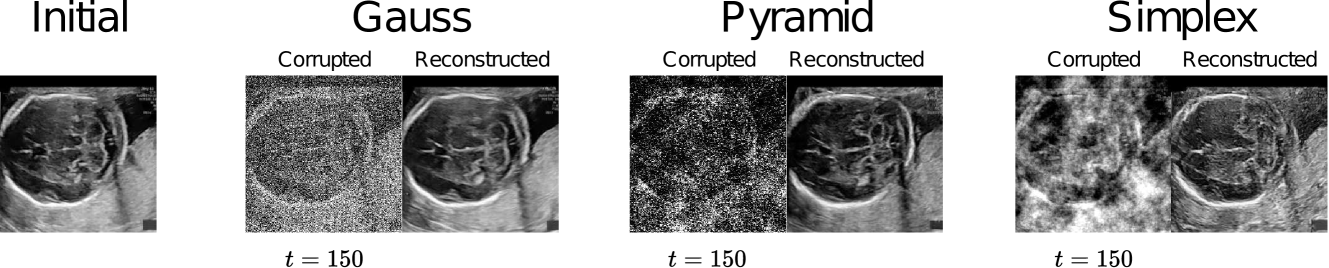

The ability to reconstruct ID images with high fidelity is an essential part of the approach, hence, we evaluate DDPMs both for generation and reconstruction. Table 1 compares DDPMs trained with different noise types for image generation based on FID using the external ID test and for image reconstruction across different corruption levels in terms of SSIM using the ID validation set. We observe that the reconstructive ability of DDPMs trained with Simplex and Pyramid decreases faster than Gaussian and they generate samples with lower fidelity. An example reconstruction is shown in Fig. 2.

In practice, is typically a Gaussian distribution. However, recent studies [30, 7, 12, 22] have shown that alternative noise distributions can significantly impact and improve medical anomaly detection tasks. In this paper, we assess the effect of three distinct noise distributions, namely Gaussian [10], Simplex [30], and Pyramid [7], on denoising diffusion models for fetal brain anomaly detection.